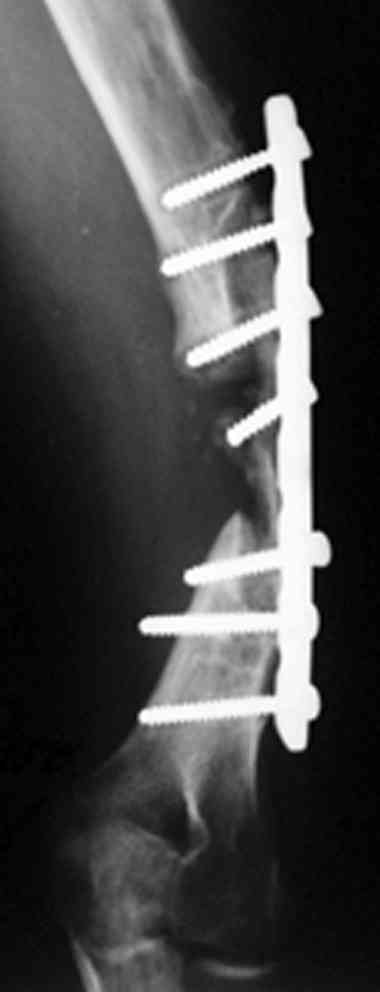

Второй случай, также после множественных операций:

пластина, аппарат, серкляж и парез нерва.

Также ревизия, из-за низкого состояния доступ был

сделан через остеотомию локтевого отростка.

Ложный сустав фиксирован двумя локинг плейт с

аутокостной пластикой, также через два месяца увидели признаки консолидации.

Движение в суставе разрешили в две недели.